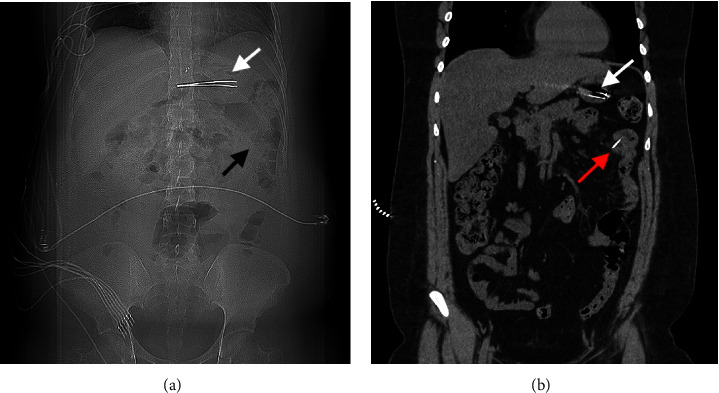

导言:异物(FB)摄入是临床实践中经常遇到的情况。大多数误食的异物通常会自行排出,无需干预。内窥镜取出异物是创伤最小的方法,只有极少的 1%需要手术干预。病例介绍。我们介绍了一例 30 岁男性的病例,他摄入了位于胃部和小肠的多个 FB。虽然通过内窥镜成功切除了胃中的 FB,但由于穿孔问题和专业知识有限,切除小肠中的第二个 FB 证明具有挑战性。考虑到患者之前曾因手术治疗导致大切口疝,医生不建议进行手术切除。因此,在外科医生和介入放射科医生(IR)的共同决定下,在 IR 技术的帮助下采用了透视引导下的切除方法:本病例凸显了在内窥镜和外科手术均不可行的情况下,采用创伤较小的替代方法的可能性。

Introduction: Foreign body (FB) ingestion represents a frequently encountered scenario in clinical practice. Most ingested FBs typically pass spontaneously, requiring no intervention. Endoscopic removal stands out as the least invasive method, with only a minimal 1% needing surgical intervention. Case Presentation. We present a case of a 30-year-old male who ingested multiple FBs located in the stomach and small bowel. While successful removal of the stomach FB was achieved through endoscopy, the second FB in the small bowel proved challenging due to perforation concerns and limited expertise. Given a history of prior surgical intervention resulting in a large incisional hernia, surgical removal was discouraged. Consequently, a collaborative decision involving surgeon and interventional radiologist (IR) led to the adoption of a fluoroscopic-guided removal approach facilitated by IR techniques.